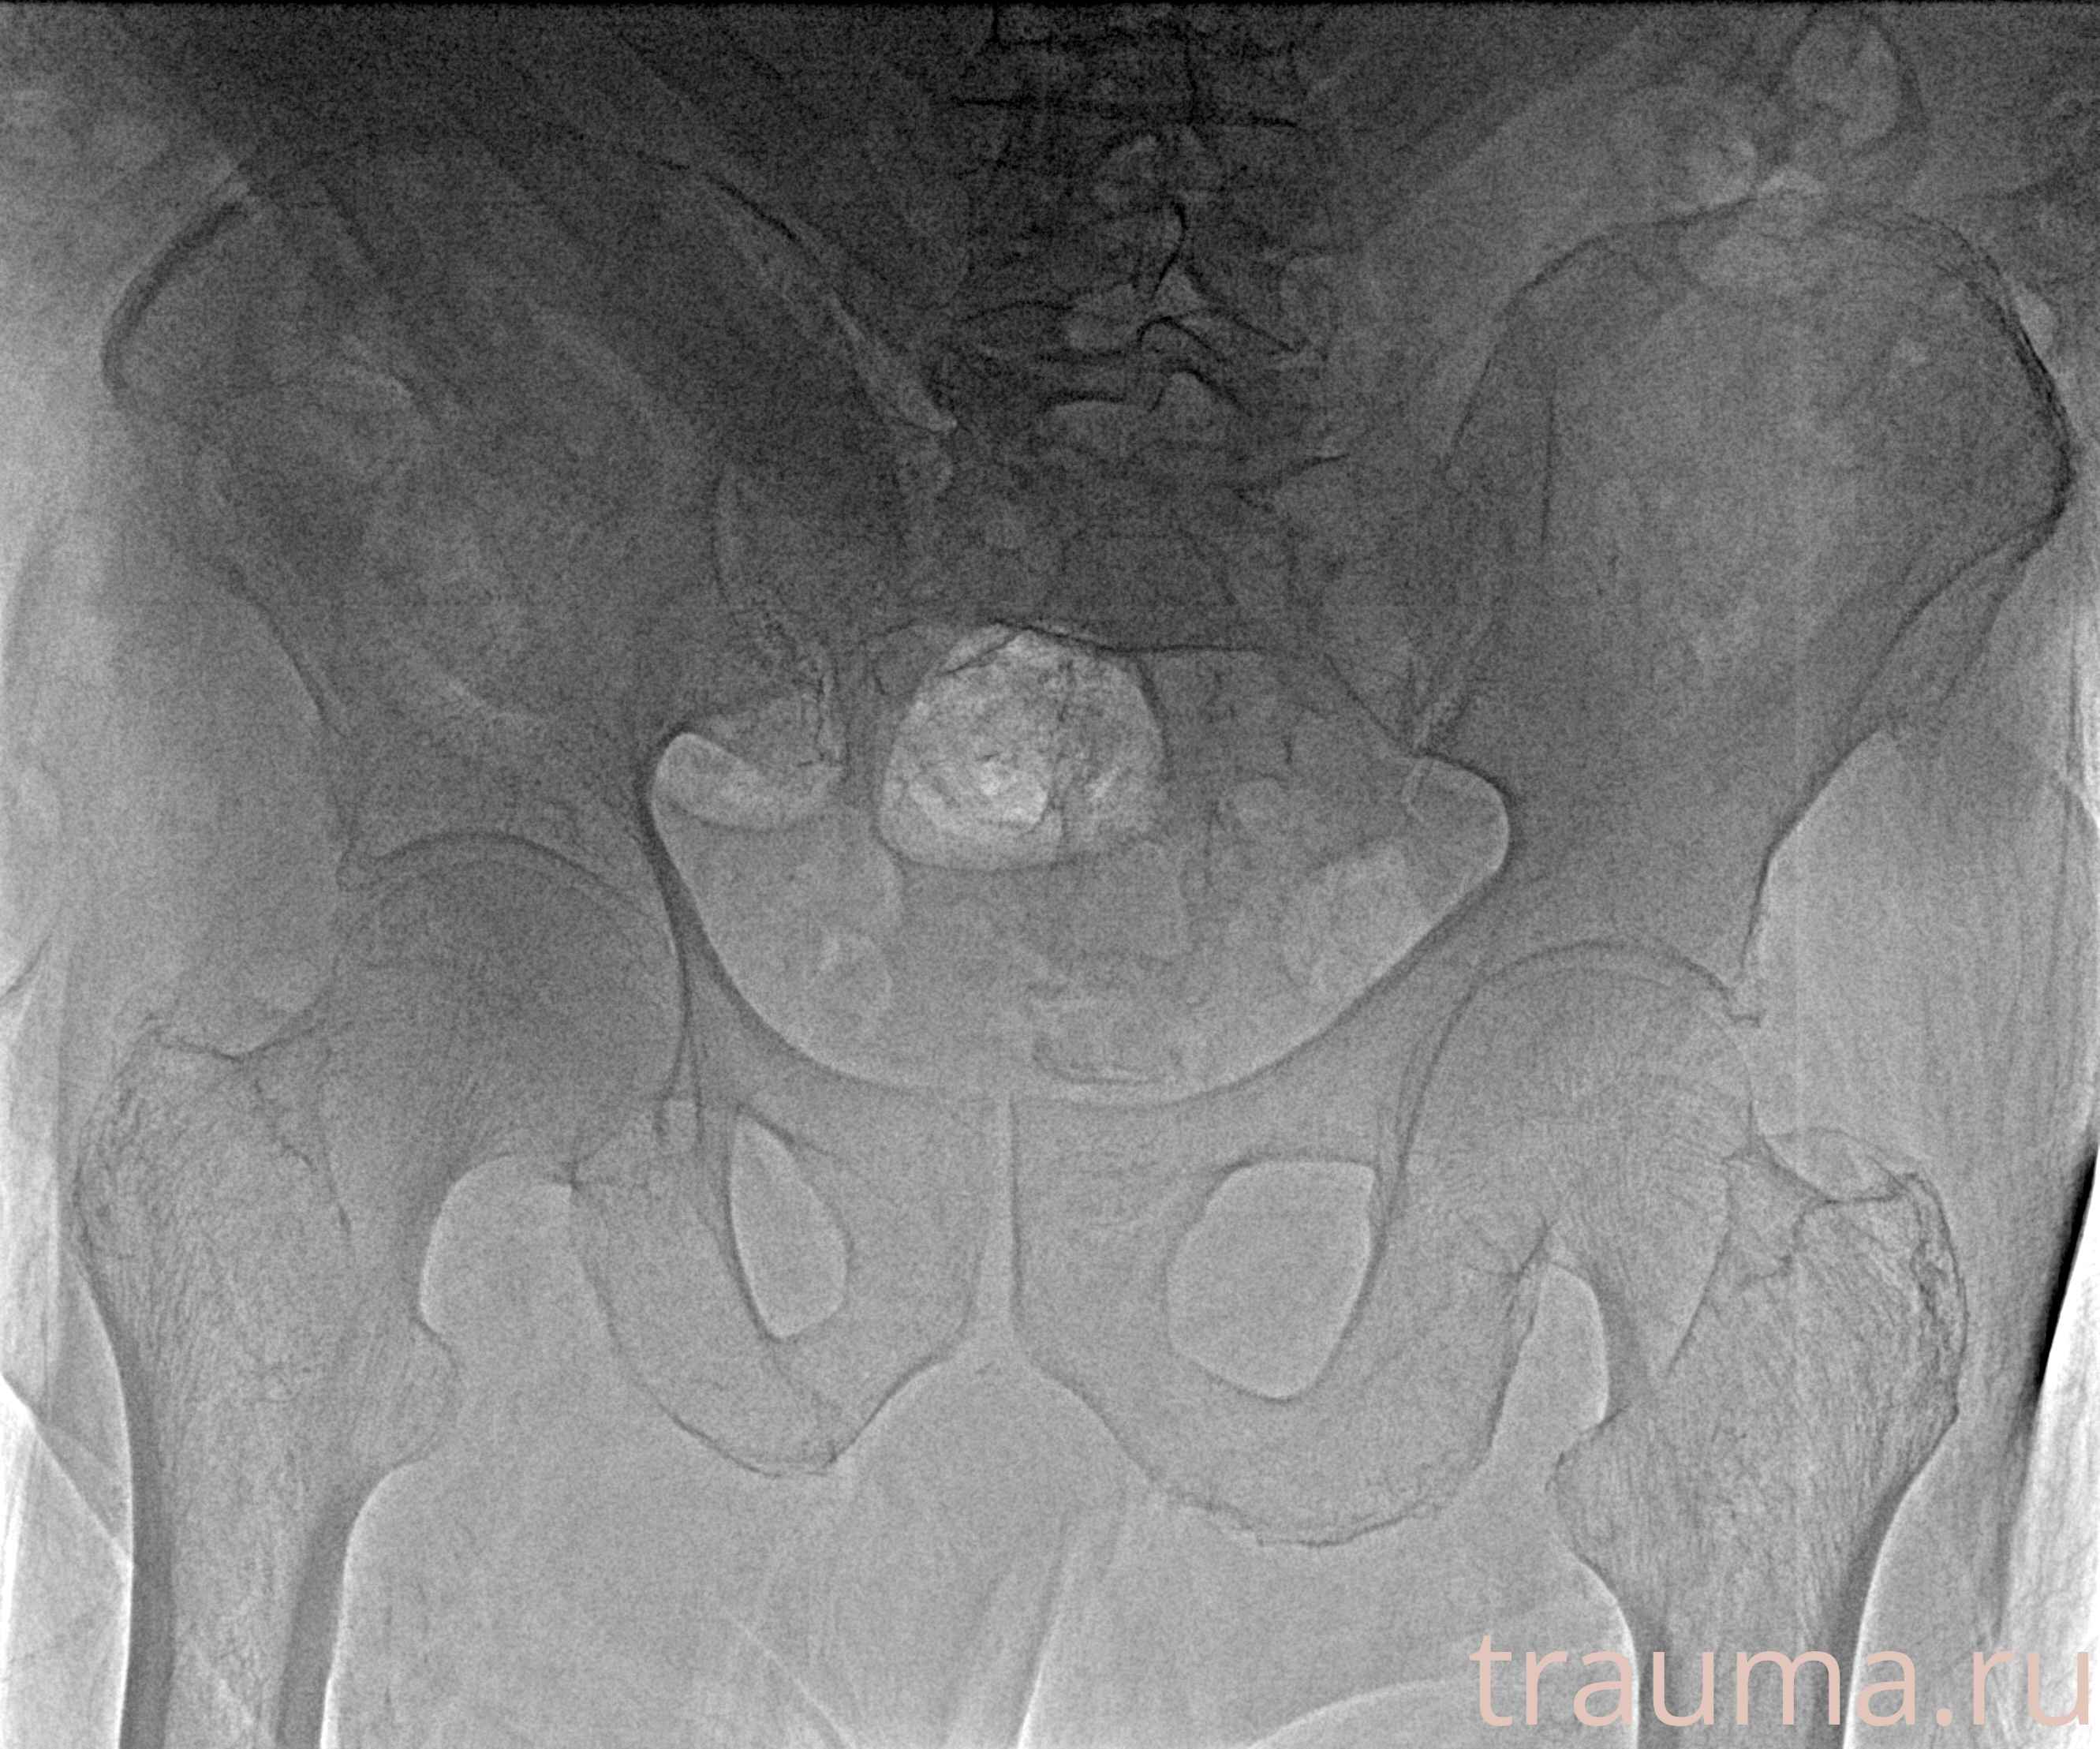

Рентгенограммы

Рентген на дому: по вашему адресу приезжает врач-рентгенолог, травматолог-ортопед с мобильным рентгеновским аппаратом, проводит диагностику травмы или заболевания, делает необходимые рентгенограммы, дает рекомендации по дальнейшему лечению. Получить качественные снимки в домашних условиях возможно благодаря уникальной методике, разработанной МосРентген Центром для института  Склифосовского